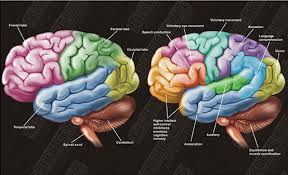

قیمت: 58٬000 تومان - دسته بندی فایل: تحقیق

قیمت: 58٬000 تومان - دسته بندی فایل: تحقیقپاورپوینت تشریح فیزیولوژیک قشر مغز (ppt) 29 اسلاید

فروش ویژه پاورپوینت حرفه ای تشریح فیزیولوژیک قشر مغز / تعداد اسلاید: 29 اسلاید